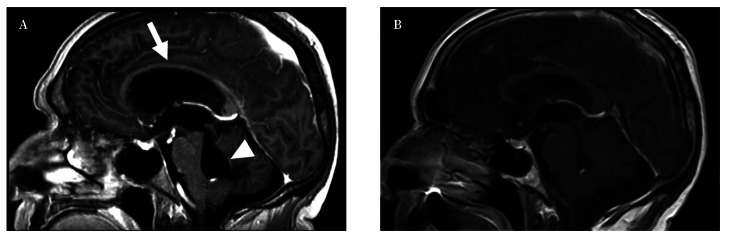

隐球菌脑膜炎是一种不常见的感染,发病率和死亡率都很高。在免疫功能正常的患者中发病十分罕见。我们介绍了一例 67 岁男性患者的病例,他因步态障碍和尿失禁的亚急性症状入院。神经系统检查显示他无法站立,记忆力受损。头颅造影显示梗阻性四室脑积水,小脑脚有神经胶质增生区域。对脑积水进行了内窥镜治疗,并采集了脑脊液样本,结果显示有新生隐球菌生长。经过内窥镜治疗,并使用两性霉素 B 脂质体和氟康唑进行为期十周的静脉抗真菌治疗后,患者病情有所好转。抗真菌药物可用于治疗免疫功能正常患者的隐球菌性脑膜炎。在极少数情况下,它会出现脑积水,这种情况需要使用脑脊液引流或内窥镜技术进行手术治疗。

Cryptococcal meningitis is an infrequent infection with high morbidity and mortality. Its presentation in immunocompetent patients is rare. We present the case of a 67-year-old male who was admitted for subacute symptoms of gait disturbance and urinary incontinence. Neurological examination revealed inability to stand and memory impairment. Cranial imaging showed obstructive tetraventricular hydrocephalus with areas of gliosis in the cerebellar peduncles. Endoscopic treatment of hydrocephalus was performed and cerebrospinal fluid samples taken revealing the growth of Cryptococcus neoformans. The patient improved with the endoscopic treatment and after completing intravenous antifungal therapy with liposomal amphotericin B and fluconazole for ten weeks. Antifungals are used to treat cryptococcal meningitis in immunocompetent patients. On rare occasions, it presents with hydrocephalus, a situation that requires surgical treatment using cerebrospinal fluid diversions or endoscopic techniques.